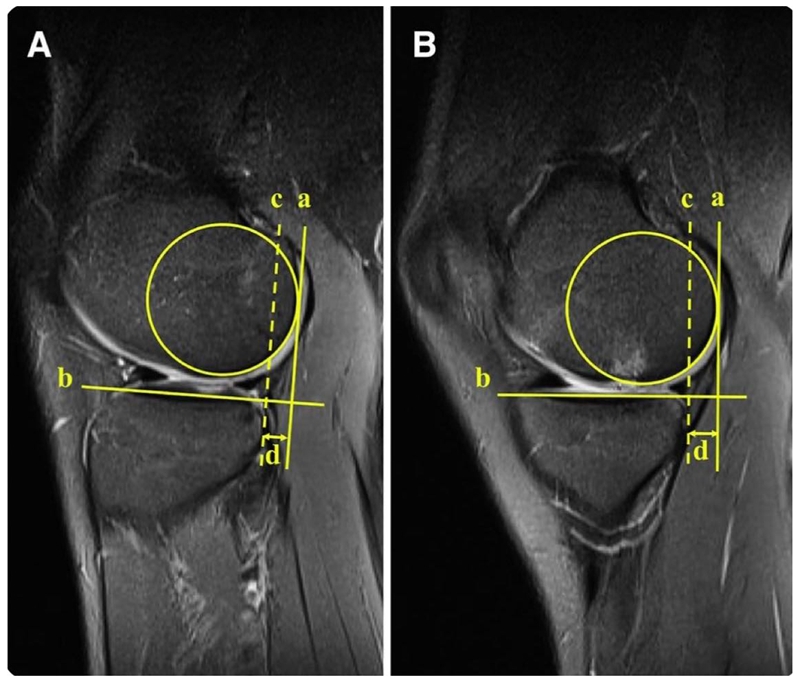

研究团队通过影像学测量发现,由术前MRI获取的外侧胫骨平台前移可用于预测急性ACL损伤后的高度旋转不稳定,外侧胫骨平台前移(≥6mm)是急性ACL损伤后高度旋转不稳定的独立危险因素,而手术治疗前空档期的长短和外侧半月板撕裂是慢性ACL损伤患者高度旋转不稳定的危险因素。

胫骨平台前移(A)外侧 和(B)内侧的测量方法

相关研究题为“Anterior Tibial Subluxation of Lateral Compartment Is Associated With High-Grade Rotatory Instability for Acute But Not Chronic Anterior Cruciate Ligament Injuries: An Magnetic Resonance Imaging Case-Control Study”,已在Arthroscopy杂志上发表。刘安医师为本文第一作者,吴浩波主任医师为通讯作者。